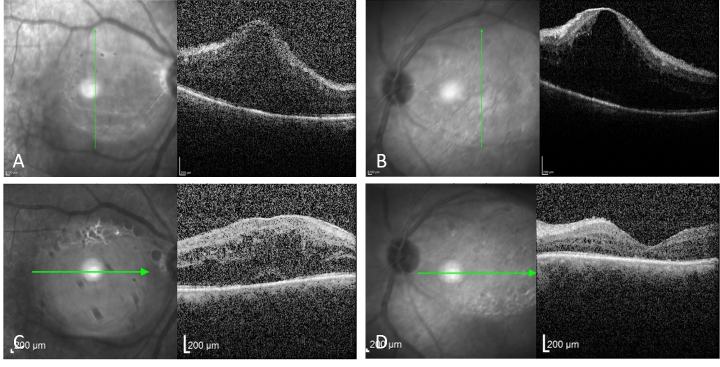

Case report: A 51-year-old man with a past medical history of HL presented with blurred vision, asthma, and bilateral yellowish eyelid lesions. The eyelid lesions and asthma appeared 10 years after being diagnosed with HL. Physical examination was significant for multiple subcutaneous and firm eyelid masses in addition to the presence of pre-auricular and submandibular lymphadenopathies. Ophthalmic examination revealed bilateral intermediate uveitis and mild macular edema. Further systemic evaluations, including laboratory testing and imaging, were normal. Excisional biopsy of the eyelid lesions was performed and the histopathologic examination was consistent with the diagnosis of AAPOX.